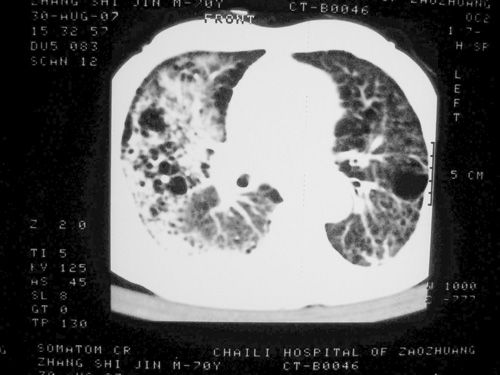

老年男性,70岁。煤矿工人20年。一周前咳嗽、发烧,拍x片考虑矽肺可能。始终咳嗽行ct检查,发现弥漫性病变,似感染但密度很高,细支气管肺泡癌无法排除,请老师给予指点。

一般矽肺多为双肺融合状,团块状高密度结节影.并散在多处小结节影.可这个病人只表现在单肺,并没有融合结节影.一周前的x片没显示大片高密度影,可定位扫描时(图象忽略传了),右肺已经清晰显示大片高密度影.作比较感觉是新病灶.可实际表现又不象,所以才拿来让各位老师看看.

矽肺,两肺间实质炎症,蜂窝肺。

矽肺  两肺间质性炎症伴纤维化(蜂窝肺)